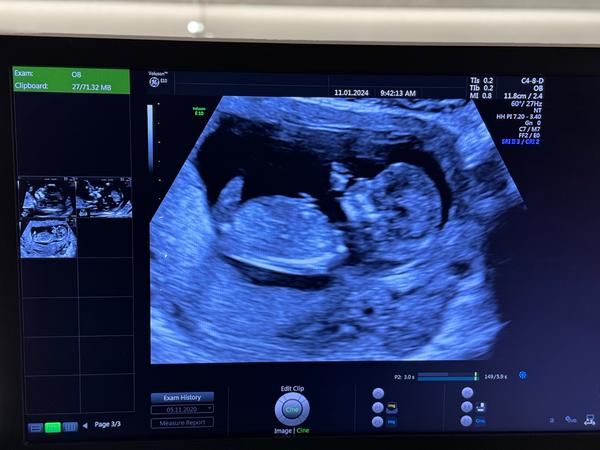

Dokážete odhadnout pohlaví miminka z ultrazvuku?

Ahoj holky, zřejmě dost častá diskuze a otázka. Ale zajímá mě názor “zkušených” rodiček, zda by si dokázaly tipnout na fotce z ultrazvuku pohlaví miminka i u mě? Jde mi jen o tipy, já pohlaví vědět nechtěla a teď jsem tak zvědavá, že se asi pana doktora při příští kontrole zeptám :D

Ale zase se přiznám, že jsem se minule tak na ultrazvuku (18tt) soustředila a žádný výběžek neviděla, každopádně to jsou opravdu jen moje hry s myšlenkami :D

@kaktus092 Je pravda, že ten výběžek nám pan doktor okomentoval, že je u kluka a u holky ještě v tom týdnu stejný a to snad někde v 10tt 😀 dále už jsme nikde nic neviděli. Ale pořád váháme, zda nepočkáme do porodu na překvápko